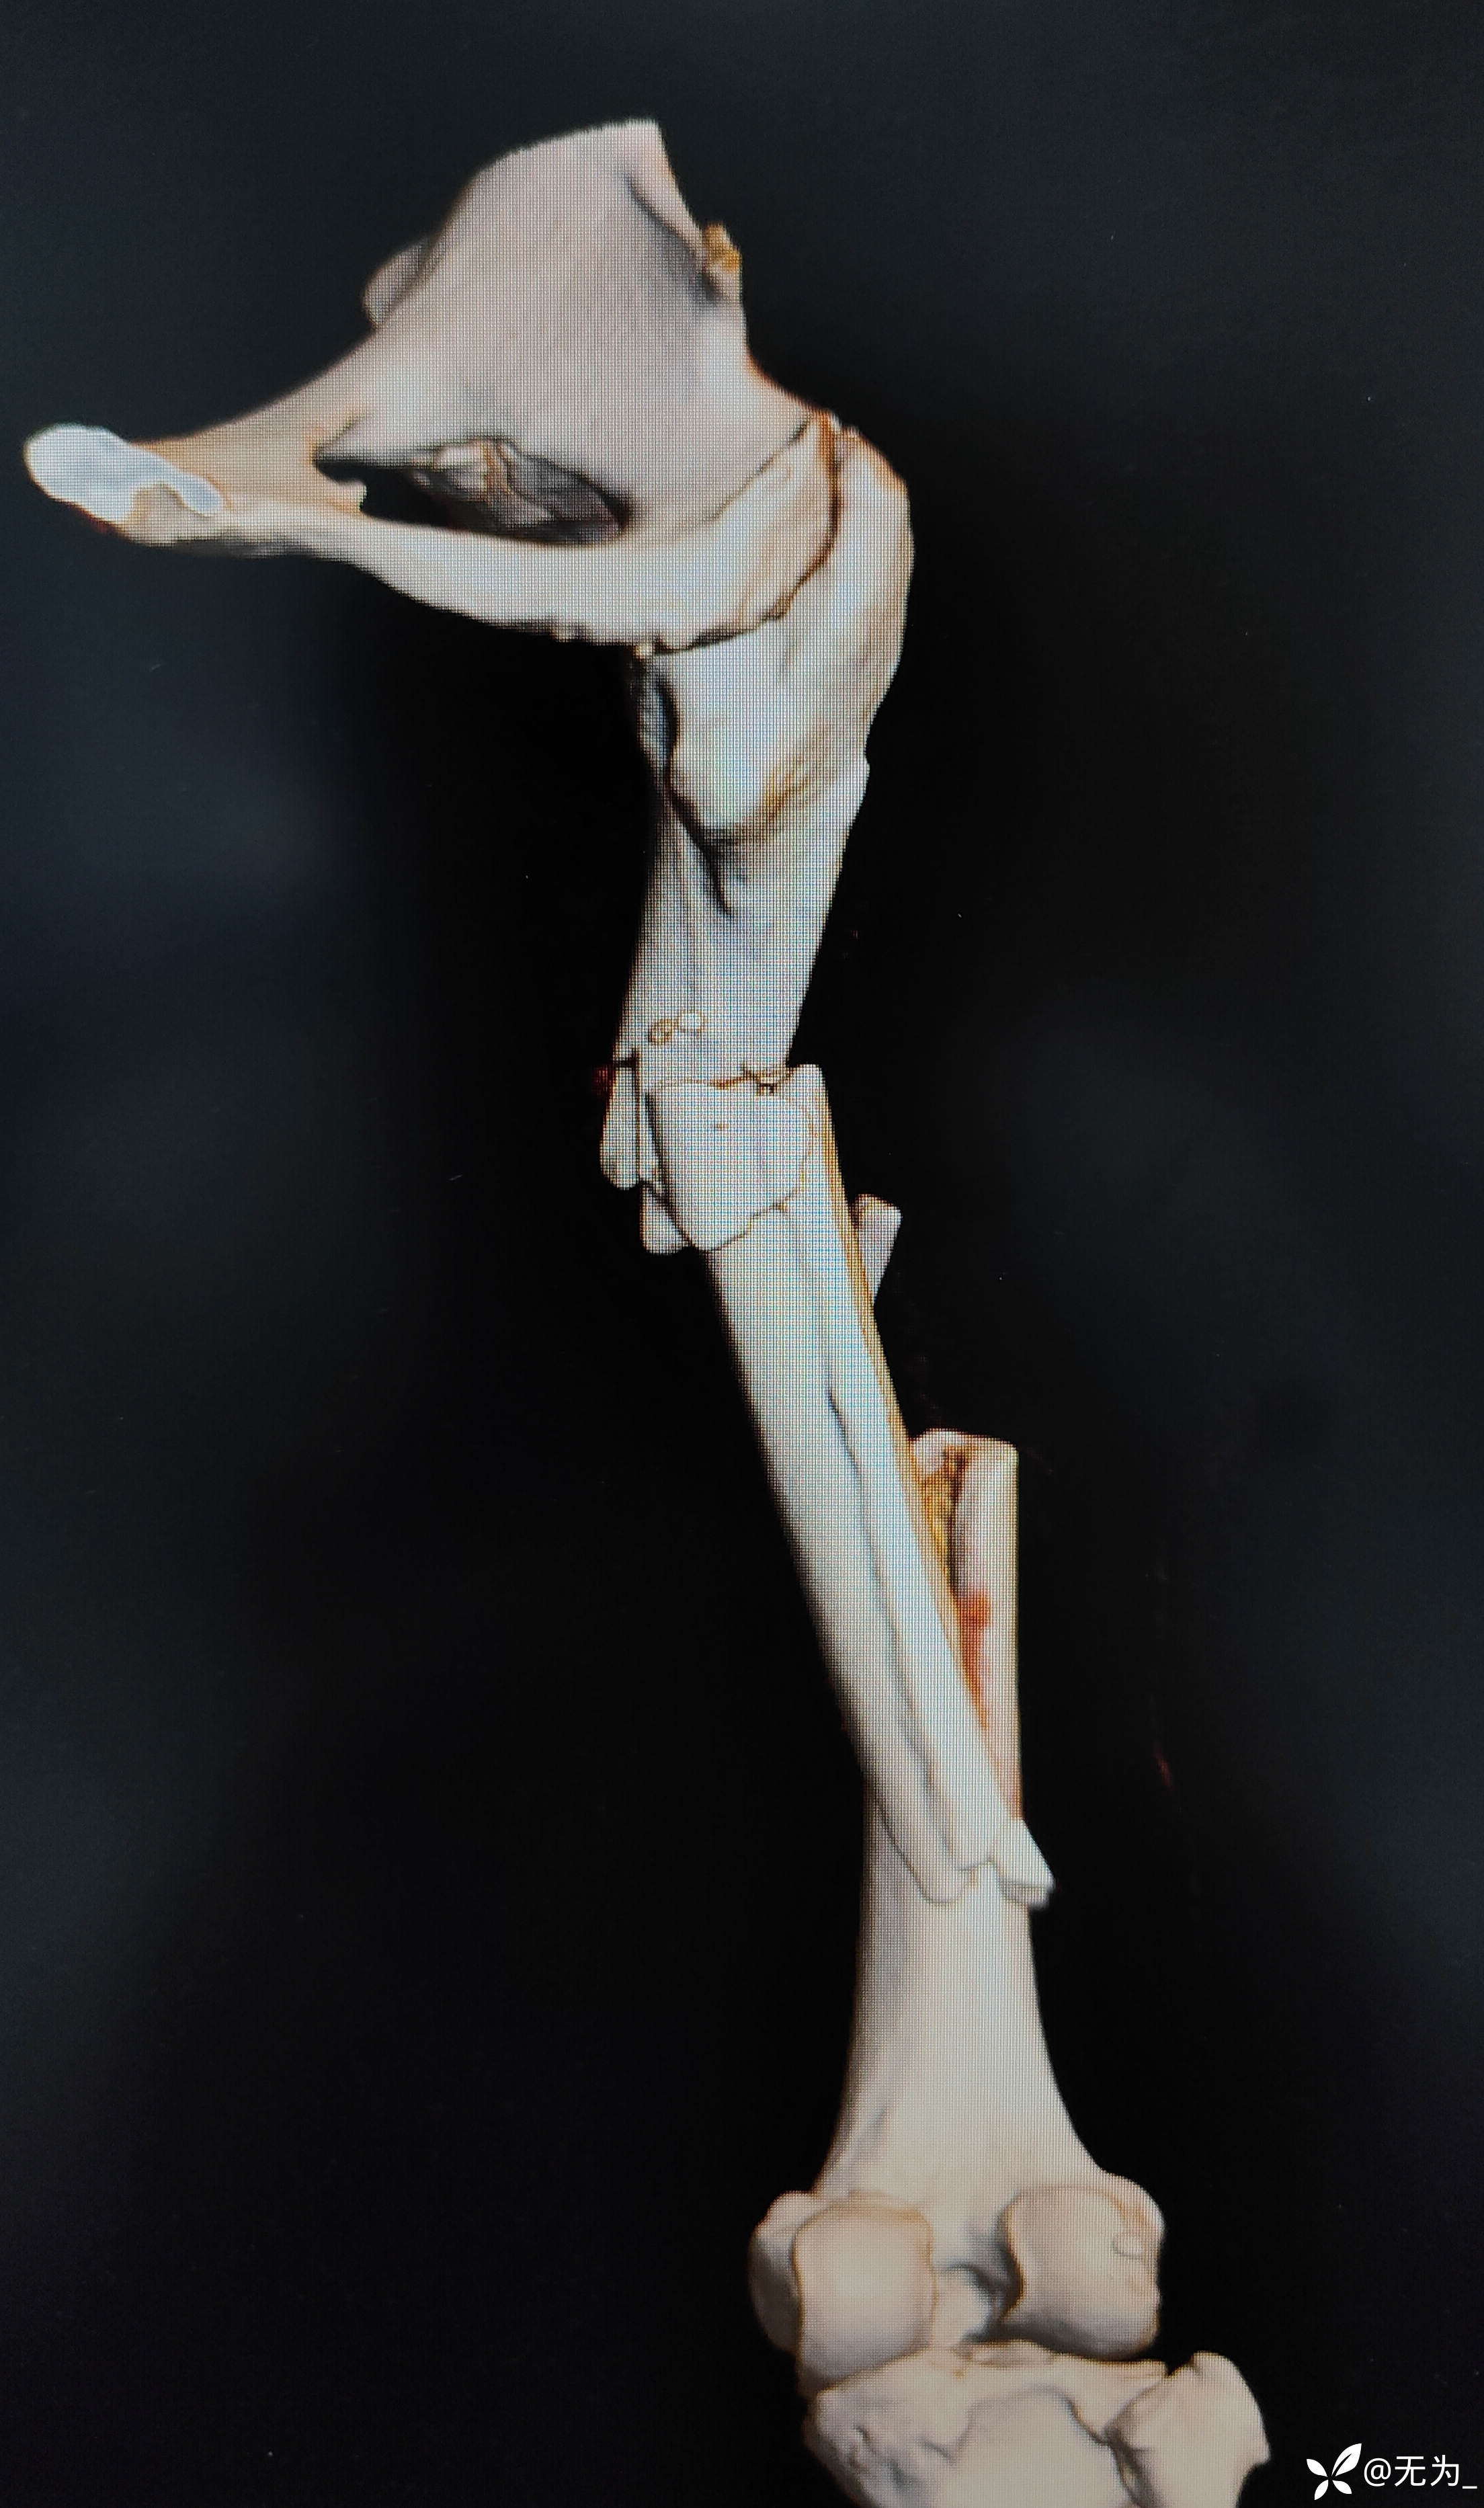

三段骨折,复位困难且时间长,患者取侧卧位,取大腿外侧切口,切开以后大量肉芽组织,清理折断,牵引复位,远折断钛揽固定,近折端钳夹复位,开孔、扩髓,置入髓内钉,螺钉固定,内侧骨块未处理伴骨缺损,未植骨避免感染。